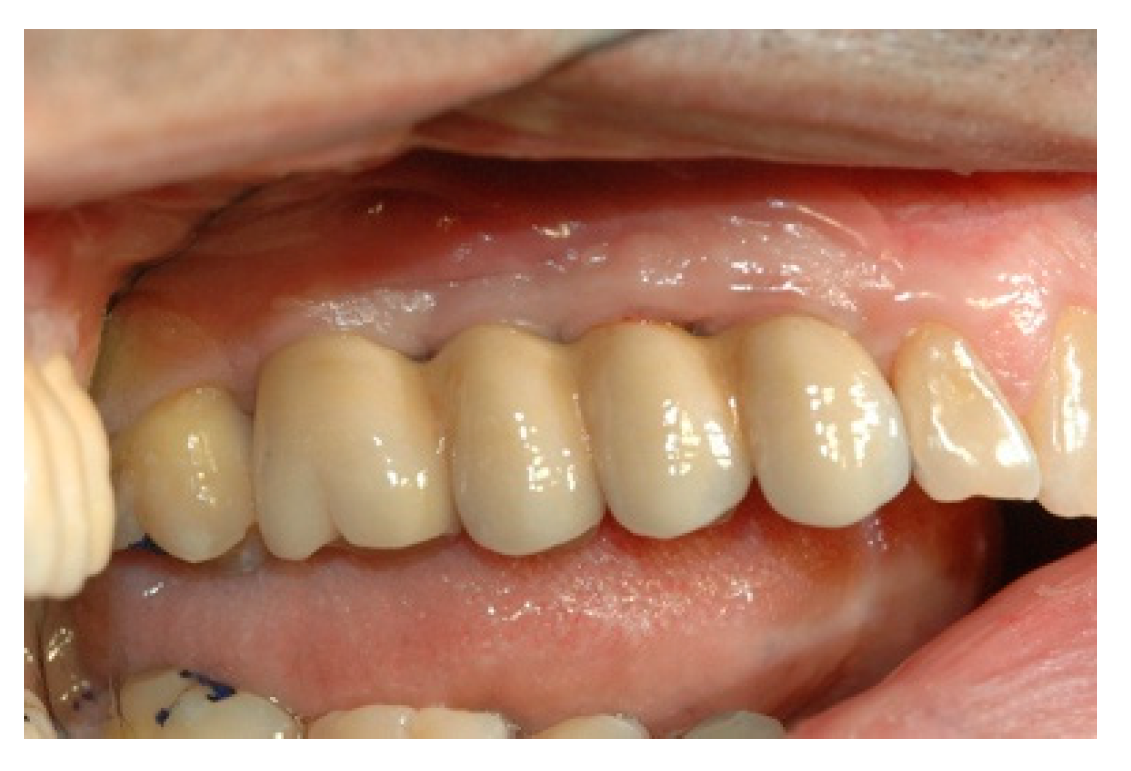

When the prosthesis was positioned, the mesostructure was fixed by tightening the screws with a torque wrench at 30 Ncm, and the superstructure was cemented by carrying out a radiographic check to evaluate the structural coherence (Figure 12, Figure 13 and Figure 14).

Figure 12. Cementing the superstructure.

Prosthesis 02 00023 g012

Figure 13. Cementing the superstructure.

Prosthesis 02 00023 g013

Figure 14. Cementing the superstructure.